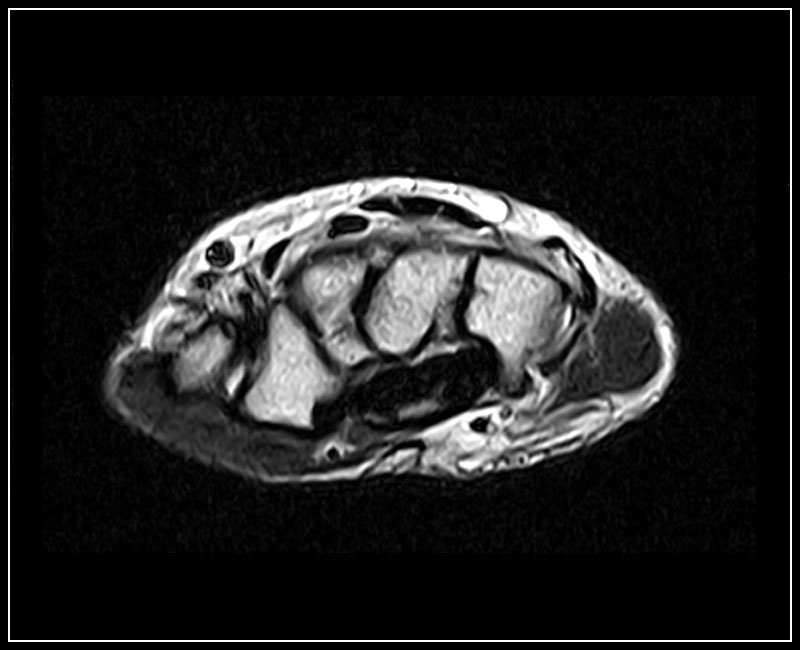

Klinické snímky